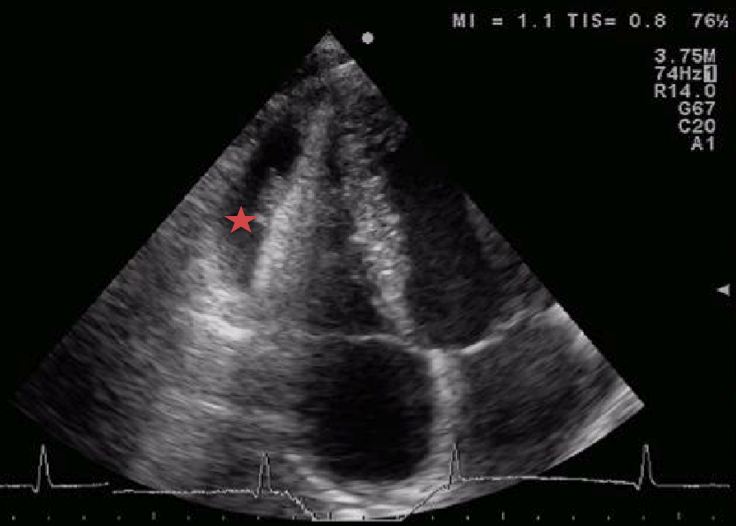

L�ecocardiografia ha messo in evidenza un versamento pericardico non rilevante emodinamicamente e una peri-miocardite (Figura 1 e Figura 2).

Figura 2. Ecocardiografia a riposo. Versamento pericardico con presenza di tralci fibrosi (stella).